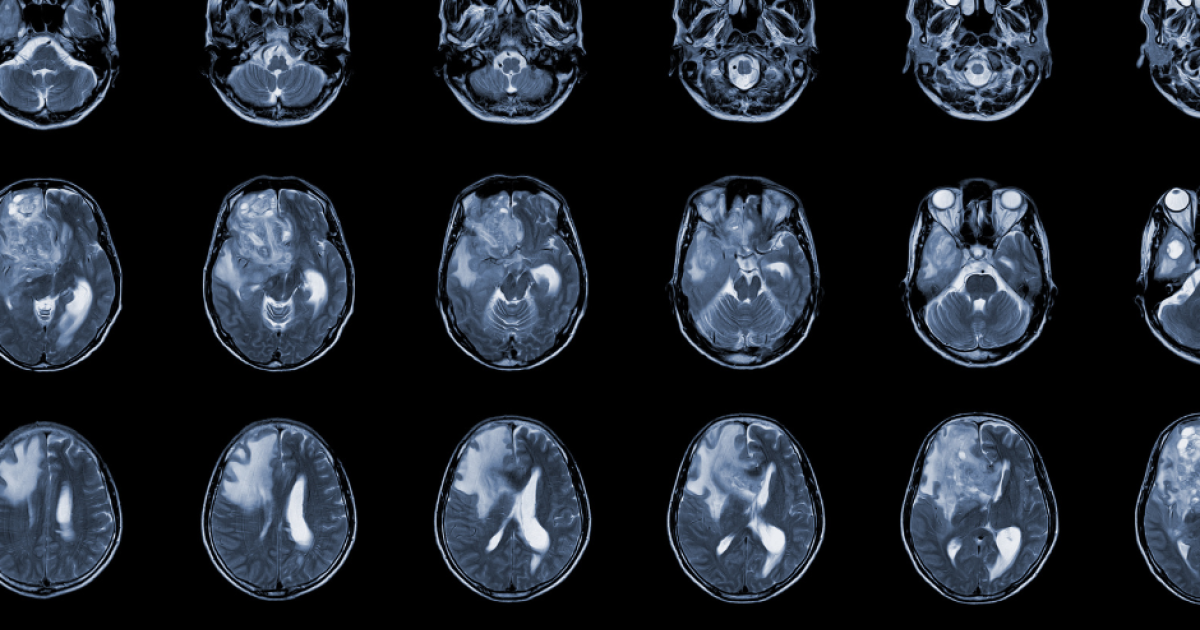

Glioblastoma (GBM) is the most aggressive primary brain tumor, with a median survival of less than 18 months despite surgery, radiation, and chemotherapy. This project establishes a novel public-private partnership between QVQ, Amsterdam UMC, and Stichting ADORE to develop a next-generation CAR-T cell therapy for GBM. By combining a highly specific GBM-targeting CAR with a B7H3-based activation-inducible receptor (CAVIR), we aim to overcome major limitations of current CAR-T therapies, including tumor heterogeneity, antigen escape, and T cell exhaustion. This collaboration leverages complementary expertise in VHH binder development, receptor engineering, and preclinical GBM models to accelerate the translation of innovative immunotherapies.

GBM affects approximately 300,000 people worldwide each year and remains one of the most lethal cancers. Standard therapies rarely achieve long-term remission, and previous CAR-T cell therapies have shown limited efficacy in solid tumors due to heterogeneous expression of target antigens and off-tumor toxicity. The development of a safe, effective, and tumor-specific immunotherapy represents a critical societal need. Success in this project could significantly improve patient survival and quality of life while fostering innovation in European biotechnology and personalized cancer therapy.

Despite the success of immunotherapy with chimeric antigen receptor-engineered T cells (CAR-T) in hematology, several factors still hinder its application for solid tumors, such as: the heterogeneous target-antigen expression, the lack of tumor-specific targets and the reduced functional persistence of CAR-T cells. We have previously shown that dual-targeting with a CAR and a chimeric costimulatory receptor (CCR), can enhance CAR-T cell cytotoxicity and persistence but cannot overcome tumor heterogeneity. Expanding the potential of this strategy, we have developed the CTLA-4-ActiVation Inducible Receptors (CAVIR, patent EP22386075). This system exploits the activation-inducible trafficking of CTLA-4 by fusing its intracellular (IC) domain to chimeric receptors achieving their spatially controlled expression. The CAVI-R expression is induced only upon activation of T cells, for example through a CAR. This novel strategy provides with a local, tumor-specific lytic capacity, overcoming heterogeneous antigen expression patterns and improving functional persistence of CAR-T cells. Glioblastoma multiform (GBM) is a brain tumor with highly heterogeneous expression of potential targets and an urgent unmet clinical need. B7H3 has emerged as a novel target for GBM. Here, we will generate novel nanobody (VHH) binders for GBM and apply them to a CAR+CAVIR strategy. We will generate and screen new VHH binders to target B7H3 (WP1). We will incorporate them in structurally optimized CAVIR constructs, and select the optimal binder (WP2). Finally, we will generate T cells carrying an EGFRvII-CAR and the selected B7H3- CAVIR and their ability to safely improve anti-tumor function and overcome tumor heterogeneity will be assessed in in vitro and in vivo GBM models (WP3). If successful, this project will generate not only a new treatment option for GBM but also for other solid tumors and will also generate critical knowledge for the improvement of CAR-T cell therapy for non-malignant neurological diseases.